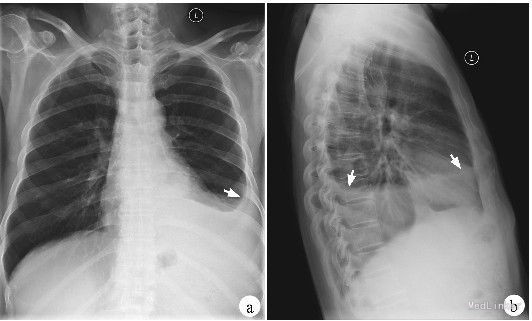

患者,女性,19岁,咳嗽,发热,左侧胸痛15天,加重伴呼吸困难5天入院。该患者于15天前无明显诱因出现咳嗽,干咳为主,伴发热,体温波动在37.5-38.0°,以午后为主,左侧胸痛明显,同呼吸运动有关,每当深吸气时加剧,在当地医院静脉滴注头孢类抗生素治疗10天后咳嗽发热症状未见明显缓解,5天前胸痛症状消失,但出现明显的呼吸困难,为明确诊断收治入院。病程中伴有盗汗、周身乏力、食欲减退。 患者既往无其他系统性疾病,其父有肺结核病史。

体温37.9°,气管右侧移位,左侧胸廓饱满,触觉语颤减弱,叩诊呈浊音,听诊呼吸音消失。其四肢大关节附近可见结节性红斑,间歇出现。 胸片:左肺胸腔积液 PPD试验:强阳性 痰涂片结果:发现结核杆菌 胸腔积液结果:淋巴细胞为主,间皮细胞<5%,蛋白质多>40g/L,腺苷脱氧酶(ADA)增高,沉渣找到结核杆菌。

诊断:结核性胸膜炎 治疗:1、胸腔穿刺把积液抽出 2、早起、规律、全程、足量、联合使用抗痨药物